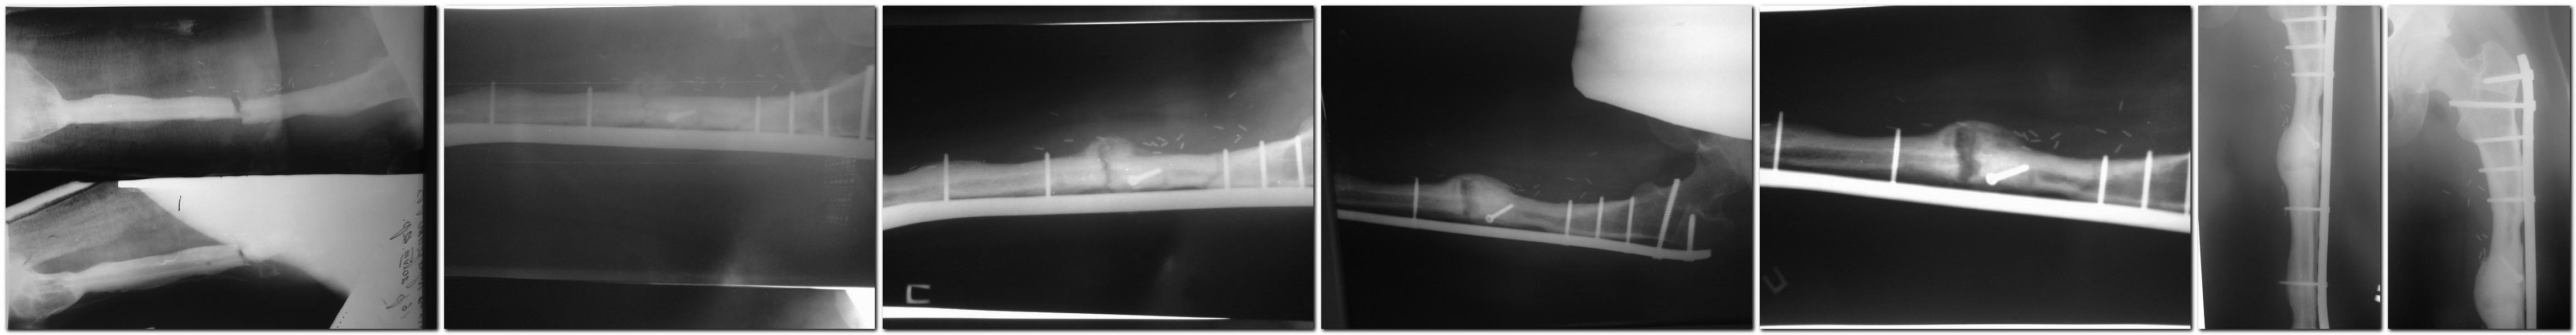

Доброго времени суток! Когда то (осень-зима, не могу найти свой пост

:))подымал вопрос про тактику лечения данной пациентки

(девочка 19 лет, остеосаркома бедра 2010 г, лечение - резекция бедренной

кости с замещением дефекта васкуляризованным малоберцовым

аутотрансплантатом, МОС длинной L-oбразной 95 градусной пластиной, через

год удаление импланта (консолидация концов трансплантат-бедро на фоне

миграции винтов). 2012 год -перелом малоберцового трансплантата, синтез

индивидуально изготовленной пластиной с угловой стабильностью. В

последующем признаки резорбции в зоне перелома. Возникал вопрос про

рецидив саркомы, нестабильность синтеза, и, соответственно, тактику

ведения больной. Больная и родственники категорически отказывались от

проведения биопсии. Тогда выбрал выжидательную тактику, лечение - курс

пролиа (Деносумаб). Снимки в хронологичной последовательности, интервал

2-3 мес. На данный момент жалоб нет, полная функция.